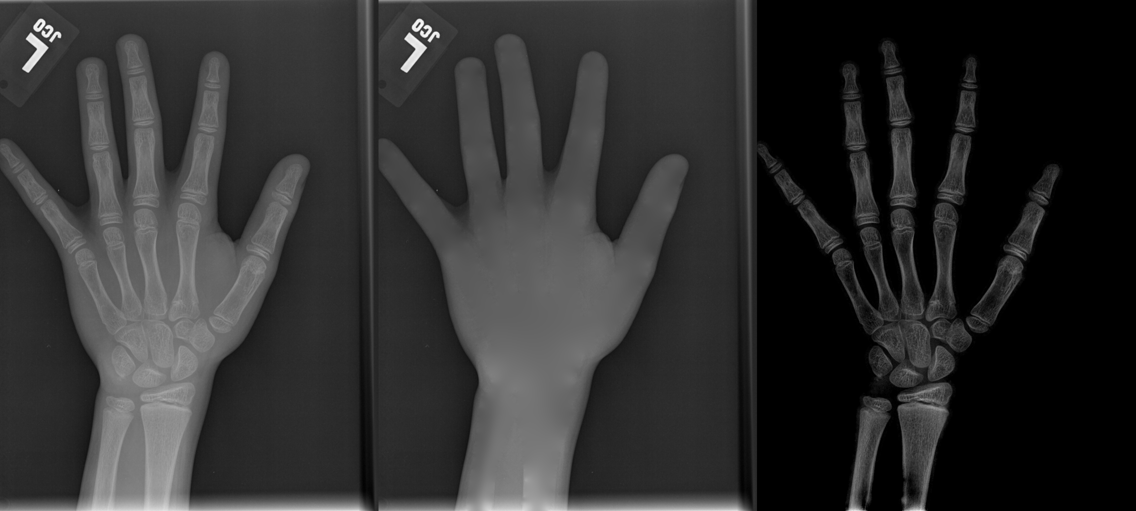

To tackle these problems, we propose to estimate the soft tissue image and bone image simultaneously without losing the linear relationship between image intensity and physical property of the imaging objects. Two examples from our method is shown in Fig. 1. The bone details are enhanced, which is theoretically guaranteed. The details of our method will be explained in later sections.

As shown in the left column of Fig. 1, bones are usually surrounded by the soft tissue. This physical configuration is similar with many natural scenes. One example is the foggy weather, as shown in Fig. 2 (a). The fog can be considered as “soft tissue” (low density) and the buildings can be considered as “bone” (high density).

We performed three experiments for our method. First, we perform our method on several X-ray images, showing our method is not restricted by specific imaging objects. Second, we compared our method with image enhancement method and dehazing method, showing that our modification of the original dehazing indeed helps in this task. Third, we perform our method on a hand X-ray image dataset, showing its effectiveness and efficiency.

Several results from our method are shown in Fig. 7. The left column is the original input image. The right two columns are the soft tissue and bone image, respectively. It can be told that the soft tissue image is smooth as we assumed. Meanwhile, the bone image has better image contrast as desired. Moreover, our method can reach real-time performance on these X-ray images. The running time of our method on these images is reported in Table I.

In each panel of Fig. 10, the input image (left) is decomposed into soft tissue (middle) and bone image (right) by our method. Although we only show the first ten images from the data set, the results for the rest images are similar.

The bone images have better image contrast since the parameter is theoretically guaranteed. Such enhancement can also be directly told by radiologists. Such enhancement is good for bone diagnosis in practical applications.